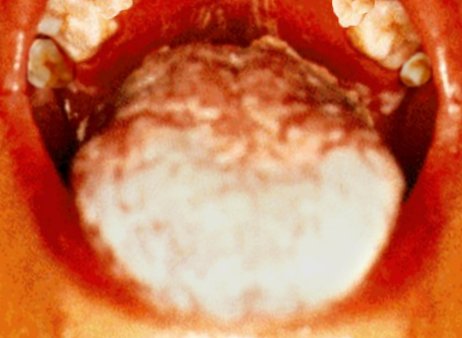

Oral thrush

The patients’ palate (top) and tongue (bottom) show the symptoms of oral thrush, an opportunistic fungal infection.

As the immune system is weakened further, serious symptoms may appear. For example: Skin rashes, fever, fatigue, night sweats, oral thrush, etc .This stage is often called “symptomatic HIV infection”. However, such relatively light symptoms will finally be followed by severe health problems. This final stage of the infection is usually referred to as “full-blown AIDS”. The immune system has broken down, and, as a result, any number of illnesses now manifest themselves. For example: Pneumocistis (PCP), an especially dangerous form of pneumonia, tuberculosis, Kaposi’s sarcoma (KS), an otherwise rare form of skin cancer, and various other cancers, “wasting”, i.e. continuing weight loss, various brain diseases, and many more, eventually killing the patient.